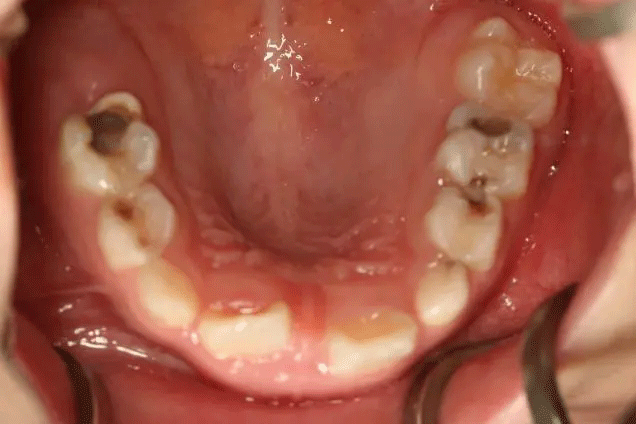

孩子1歲開始已經(jīng)出現(xiàn)齲齒

但是媽媽2年后才帶孩子就診

這時(shí),孩子已經(jīng)斷斷續(xù)續(xù)疼了3年

在門診中發(fā)現(xiàn)

來口腔科檢查的孩子

有些牙齒都已經(jīng)爛得很嚴(yán)重了

甚至牙齒幾乎都爛光僅剩下牙根

孩子不喊疼,家長(zhǎng)很少會(huì)帶來看牙